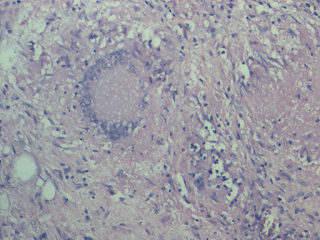

BT leprosy. Granuloma around a follicle.Lymph node

A granuloma in omentum; extensive epithelioid change, undergoing keratinisation !

![]() |

| Langhans giant cell |